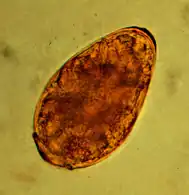

Microscopic image of an egg packet of the cucumber nematode tapeworm.

The cucumber tapeworm (dipylidium caninum) - named after its limbs resembling a cucumber seed - is up to 80 cm long and parasitizes in the anterior small intestine. The obligate intermediate host is primarily the cat flea, occasionally also the cat hair flea. The tapeworm members shed in the intestine leave the anus with the feces or by active migration. The eggs are ingested by the larvae of the insects, penetrate their intestinal wall and develop in the fat body to the fin stage (cysticercoid). Depending on the external temperature, the cysticercoid is infectious as soon as the adult flea hatches or several days later. Infection occurs by eating the fleas, whereupon the fin grows into the adult tapeworm in the small intestine. The prepatency period is about three weeks.

Infestation with cucumber nematode tapeworm can be determined by detecting the limbs in the anal region or by detecting the 35-53 μm eggs or egg packets in the feces using flotation methods. However, these detection methods are very uncertain. In one study, autopsies revealed an infestation rate of 34.5%, even though all previous fecal examinations were negative.[10]